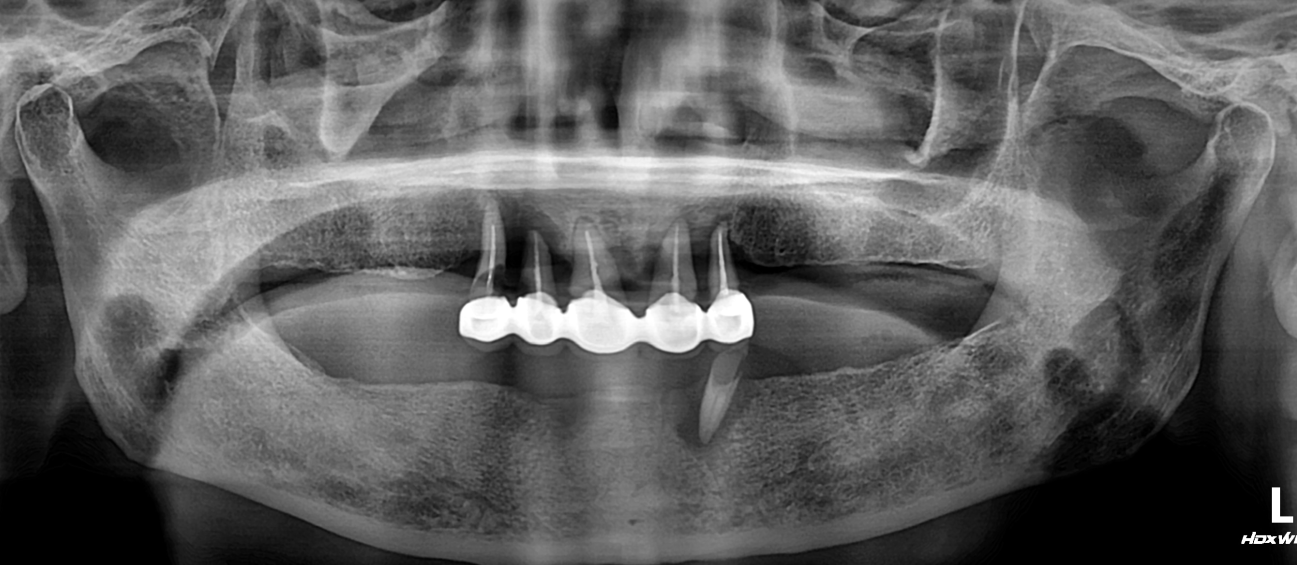

Before

임플란트